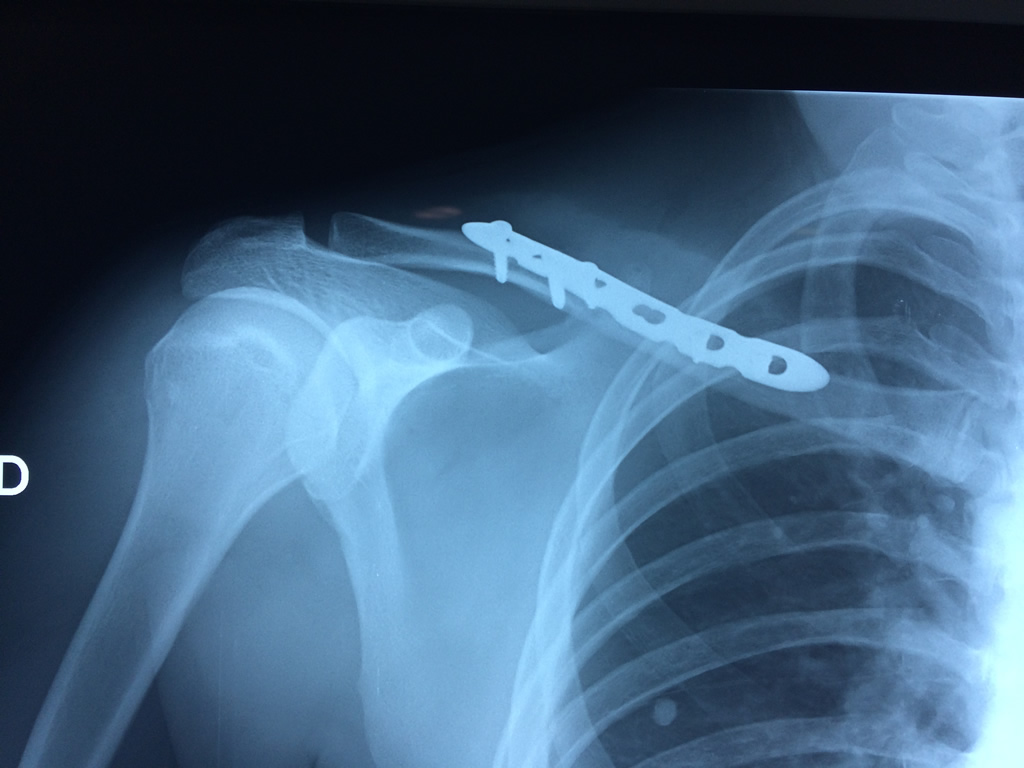

Cirugías de Calcaneo - Clavícula

La clavícula es un hueso largo, con forma de "S" itálica, situado en la parte anterosuperior del tórax. Junto con la escápula forman la cintura escapular. Se puede palpar por toda su longitud y se extiende del esternón al acromion de la escápula, siguiendo una dirección oblicua lateral y posterior.

Se considera el único medio de unión entre el miembro superior y el tórax. A pesar de su aspecto, similar al de un hueso largo, posee una estructura semejante a la de un hueso plano, ya que carece de epífisis y de diáfisis, lo que la harían entrar dentro de la clasificación de hueso largo. Carece de un canal medular propiamente dicho.